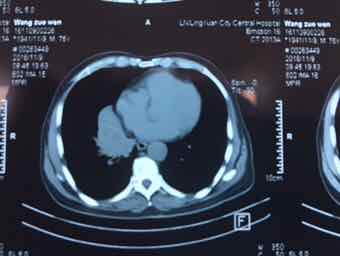

男,74岁,咳嗽咳痰3个月,无发热,无胸痛,无盗汗,无咳血。右肺占位性质待查?完善气管镜检查